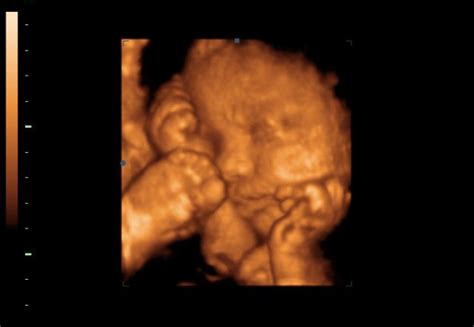

Ezen a fotón már egy 3.6 cm-es, 10-12 hetes magzat látható.

Mi történik a terhesség 12. hetében? A baba minden belső szerve kialakult. Szopogatja a hüvelykujját. Mérete olyan, mint egy lime. Nézz rám!